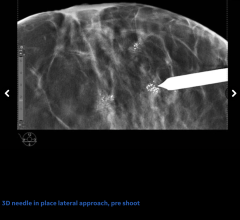

March 20, 2025 — GE HealthCare has launched Invenia Automated Breast Ultrasound (ABUS) Premium, the latest 3D ultrasound ...